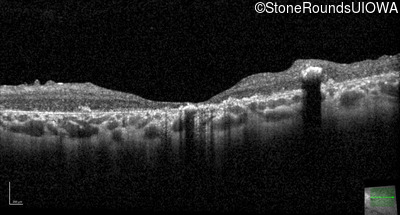

Optical Coherence Tomography - Right - 20/400 sc

Exemplar / OCT Stack